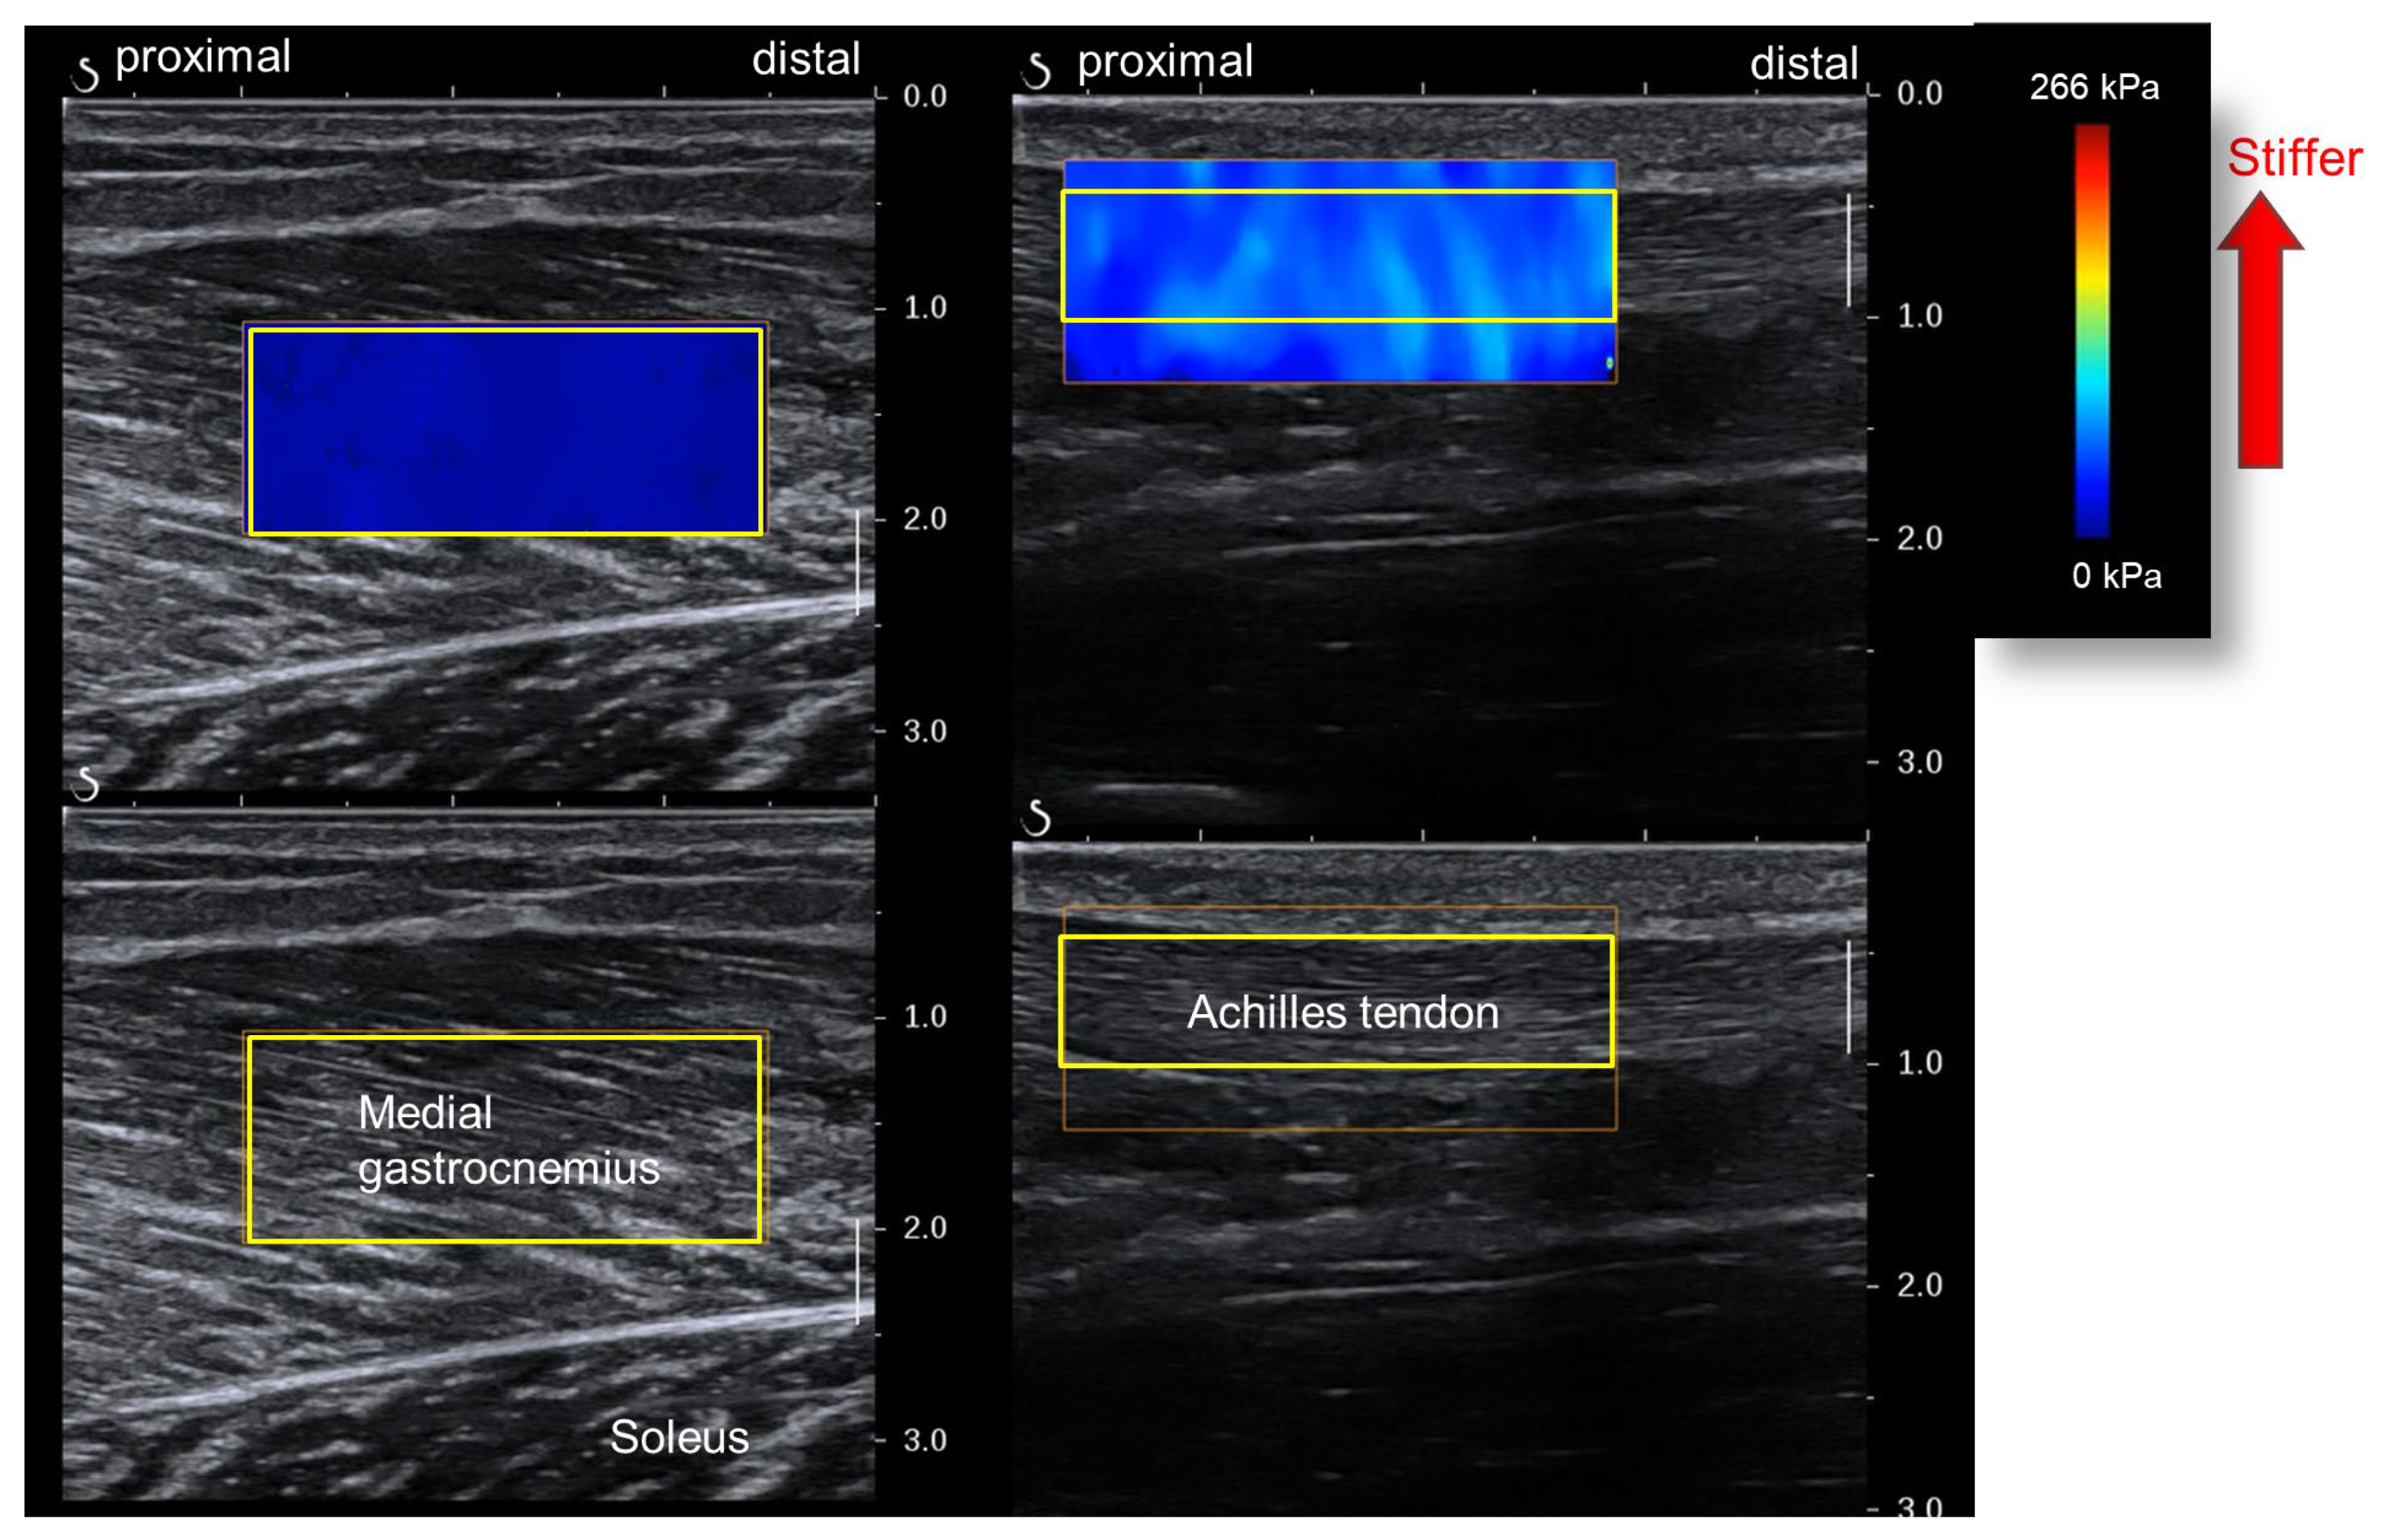

We used an elastography image analysis program (T.K.K. 5840, Takei Scientific Instruments, Niigata, Japan) to analyze the ultrasound images on a personal computer (Figure 4). We set a rectangular region of interest (ROI) for each image and obtained the mean value of the shear modulus within the ROI. The MG stiffness for each joint angle was defined as the mean of three out of the five shear modulus values obtained from the five ultrasound images, excluding the largest and smallest.

The ankle joint angle for the AT shear modulus measurement was 20° plantar flexion. The participants’ posture for the measurements was the same as that for MG stiffness, except for the joint angle. Based on previous research, the AT measurement site was the free part of the tendon distal to the distal end of the SOL’s belly [16]. Ultrasound images were acquired and analyzed similarly to those for the MG to determine AT stiffness for each joint angle (Figure 4).

Figure 4. Analysis of muscle and Achilles tendon shear moduli wave velocities (yellow squares—regions of interest [ROIs]). The muscle shear modulus is obtained from the medial gastrocnemius (left). The Achilles tendon shear modulus is obtained from the free tendon part (right).